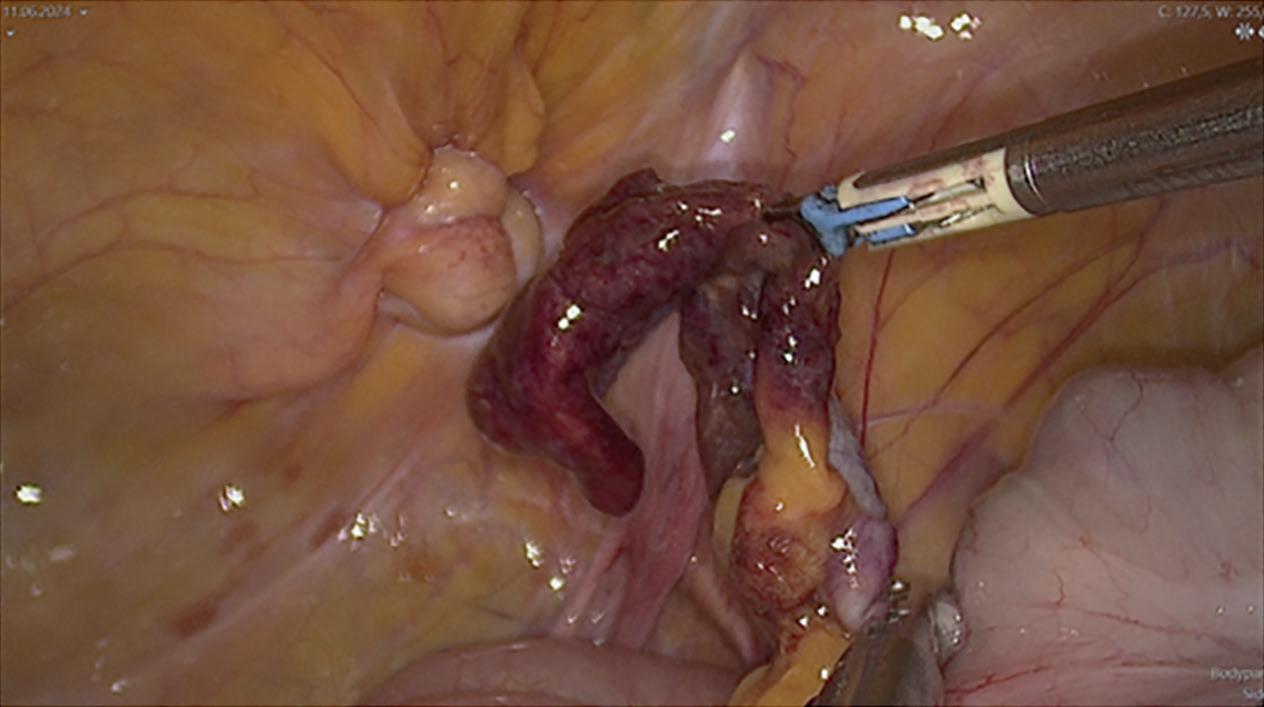

KIRURGISK BEHANDLING

I kombinasjon med medikamentell behandling, skal man alltid vurdere kirurgisk behandling, uavhengig av sykdommens alvorlighetsgrad. Målet med kirurgi er å fjerne epitelisert sinus og debridering av vevet slik at inflammatorisk vev fjernes og en oppnår bedre kontroll over inflammasjonen. For å lette det kirurgiske inngrepet, er det gunstig å først ha god medikamentell kontroll på sykdommens aktivitet (15). Det er ikke anbefalt å gjøre drenasje av HS-lesjoner med et enkelt hudsnitt. Det er en kortvarig løsning med stor fare for residiv (7, 9, 14). For en enkel inflammert noduli kan man bruke en rund biopsi-punch, i passende størrelse, for å fjerne den inflammerte follikulo-pilosebacøse enheten. Deretter gjøres lokal debridement, med en kompress for å unngå ruptur og residiv av lesjonen. Det er en enkel prosedyre, som ikke krever kirurgisk kompetanse. Teknikker som «deroofing», der man fjerne taket av lesjoner kan utføres ved inflammert noduli, abscesser eller sinustrakter. Det kan gjøres på enkle lesjoner, men også ved avansert sykdom, da som en mer omfattende prosedyre. Det kan gjøres under lokalbedøvelse, men det må vurderes individuelt. Inflammerte noduli og sinustrakter blir åpnet og hele hudområdet over lesjonen skal fjernes; man kan bruke saks eller knoppsonde for å sondere fistelsystemet. Det er viktig at det ikke blir noe gjenværende trakt. Deretter debridering med enten kompresser eller curette, før primær eller sekundær lukking. Karbondioksid-laser (CO2-laser) er også en godt dokumentert metode som brukes ved «deroofing-teknikk». Den fjerner inflammert vev med sekundær tilheling. Det er dokumentert lite residiv (11). Kronisk og mer omfattende HS-lesjoner, som residiverer til tross for nevnte behandlinger bør behandles på en mer aggressiv måte og noen ganger med rekonstruktiv kirurgi. Det gjøres en omfattende kirurgisk eksisjon av affisert område med noe margin, vanligvis på operasjonsstuen og i lokalbedøvelse. En aggressiv kirurgisk behandling innebærer å fjerne follikulo-pilosebacøse enheter, alt inflammatorisk vev og fistlene til det er friskt subkutant vev. En trenger ikke nødvendigvis gå helt ned til muskelfascien. Det er lite residiv ved radikal eksisjon, og derfor